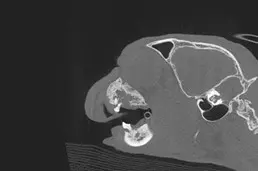

Left – right caudal maxilla in an 8 year old cat. Right – same cat with CBCT imaging. Significant more bony changes are evident on the CT image